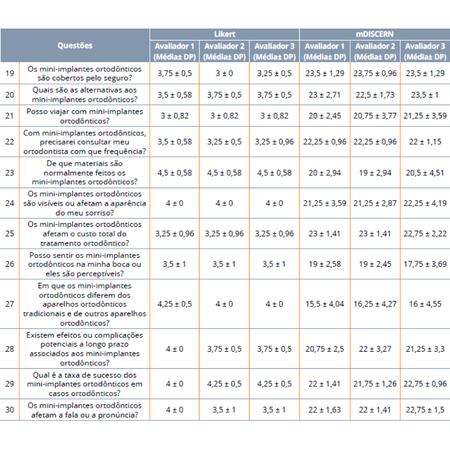

Introduction: In this era of artificial intelligence, the increasing competition has significantly enhanced the power of AI chatbots, which have been integrated into various fields, including orthodontics. They can be a good option for enlightening topics of curiosity before or during treatment, as they are easily accessible by patients. However, their reliability remains a concern. Miniscrews, or Temporary Anchorage Devices (TADs), frequently used during orthodontic treatments, are among...

Leia mais